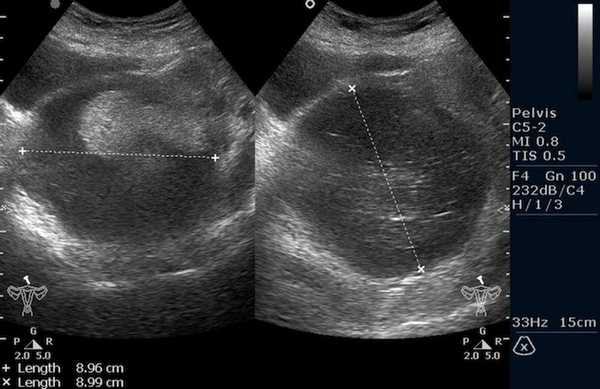

Рисунок 3. - тератома яичника а -УЗИ, б — МРТ.

- УЗИ. «Ультразвук» нужен для того, чтобы выявить первичный очаг как гонадной (в половых органах), так и внегонадной герминогенной опухоли. Его также проводят в ходе терапии, чтобы оценить ее эффективность.

Рисунок 8. КТ органов брюшной полости - на снимках вы можете увидеть опухоль яичника.

![Тератома яичника (УЗИ малого таза)]()

Тератома яичника (УЗИ малого таза)

Самая часто диагностируемая герминогенная опухоль - это дисгерминома. Преимущественно ее обнаруживают во второй декаде жизни. У маленьких девочек встречается редко. Такое заболевания сравнительно быстро распространяется, поражая брюшину и второй яичник. Обычно новообразования односторонние, имеют большие размеры. В связи с этим частое явление - разрыв капсулы новообразования.